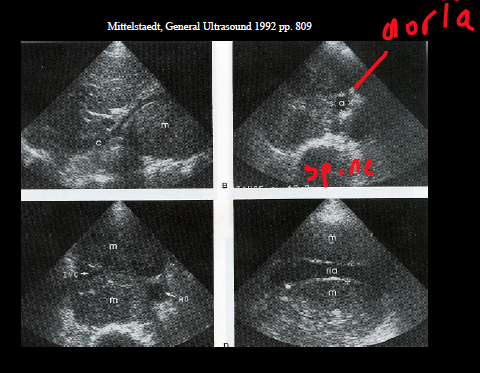

what are these examples of?

retroperitoneal lymph nodes

peripancreatic lymph nodes (pt has history of lymphoma)